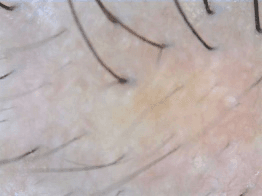

| Clear | ![]() | ![]() | ![]() | ![]() |

| Almost Clear | ![]() | ![]() | ![]() | ![]() |

| Moderate | ![]() | ![]() | ![]() | ![]() |

| Poor | ![]() | ![]() | ![]() | ![]() |

| Severe | ![]() | ![]() | ![]() | ![]() |